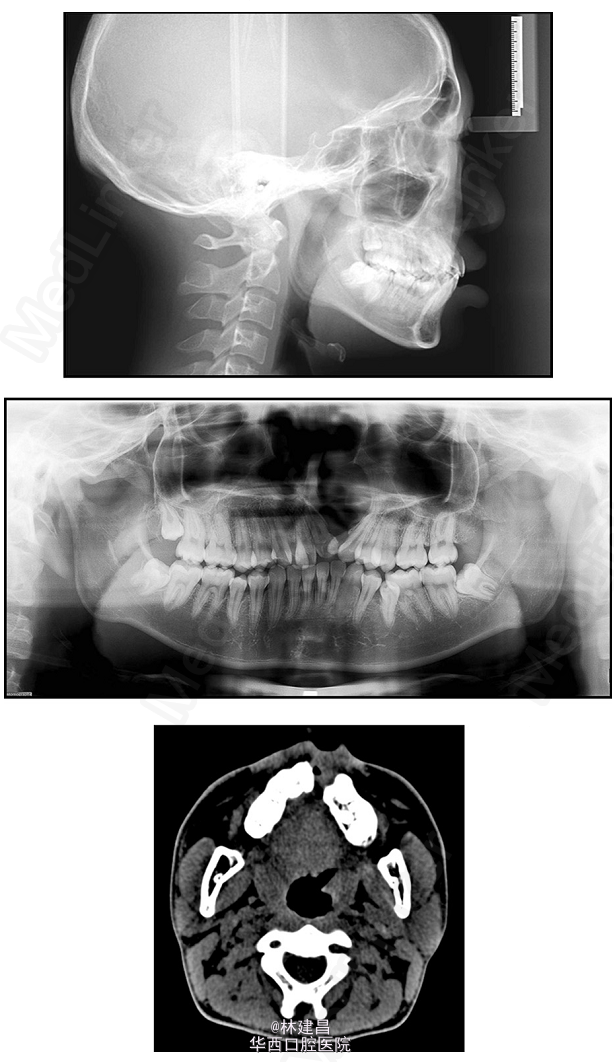

唇腭裂患者的联合治疗一例

腭裂

患者为18岁男性,面形凹,上颌骨发育不足,有一处重度牙槽突裂,因面部不美观,来正畸科求治。综合评价其病情后,为患者提供了手术和非手术两种方案,患者最终决定了非手术方案。此后患者的正畸治疗包括了扩弓、拔牙和牙周修复会诊。正畸治疗使用了新亚MBT托槽0.022x0.028(国产托槽也有好货!)配合微种植钉,排齐整平恢复I类磨牙关系。治疗完成1年后复诊。